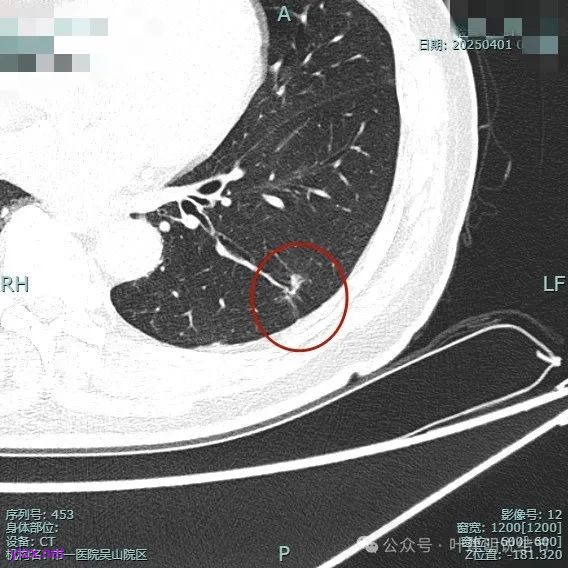

整体纵向仍偏长条些,实性部分不太致密,边上磨玻璃成分的轮廓与界限不太清楚,毛刺显得长。

仍有支气管扩张,但较2024年时密度感觉低了点。

密度较淡且缺乏收缩力。

密度杂乱,血管进入,但血管说不上明显异常增粗,磨玻璃成分淡而瘤肺界限欠清。

总体较之前密度有减低,缺乏聚拢性。

我考虑较前好转,应该是慢性炎,建议9个月后再复查。